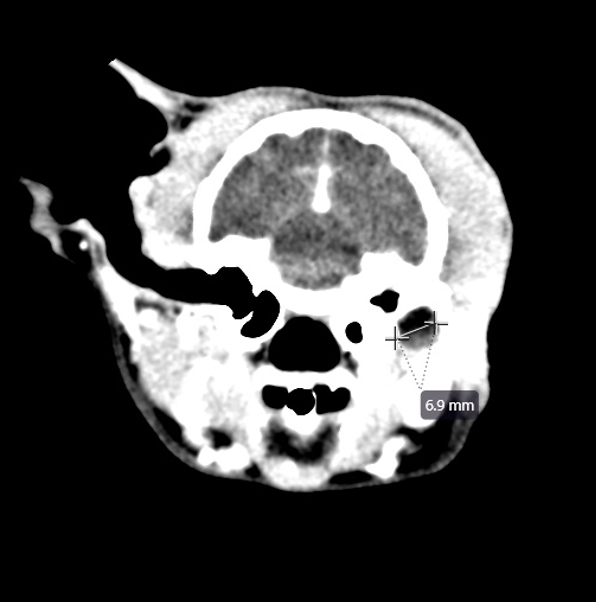

Since then, Kiki has had recurrent draining tracts/abscesses at her TECA-BO with multi-drug resistant bacterial on culture results. Kiki was first seen at BARC on March 18, 2025 for a CT. The CT showed a 6.8mm x 7.8mm region of rim-enhancing tissue at the base of the left ear just lateral to the tympanic bulla suggesting a region of persistent infection/inflammation, with some inflammation extending lateral to the region. No cutaneous drainage was noted at the time of CT.